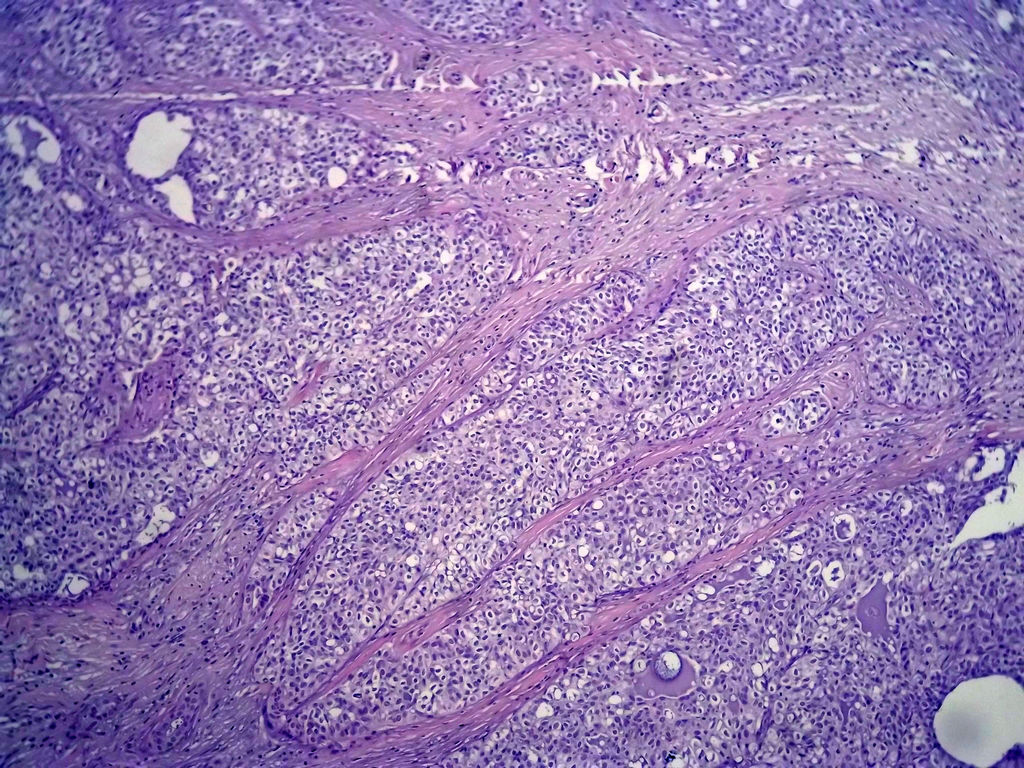

今天的一例术中冰冻。女,49岁,乳腺肿块。人气不旺,换个标题

腺病?癌?其他?(12楼常规,24楼免疫组化及会诊结果)图1

标签:浸润性导管癌 分泌癌 硬化性腺病

乳腺分泌型癌

导管是乎可见双层上皮,部分上皮增生并有一定异型,考虑硬化性腺病,待石蜡。

导管可见双层上皮,部分上皮增生并有一定异型,考虑硬化性腺病

冰冻符合乳腺腺病

腺体与腺体之间的对比差异太大,不放心,不除外是癌,如果是我的病例,再次取材冰冻

占楼传常规1-11为冰对。

后取的恶性特征明显多了,神经内分泌癌?

浸润性导管癌。冰冻切片的诊断是很困难,直接诊断癌风险很大,但是在明显正常的导管间这种成片、成巢有腔的细胞团块也不是良性的表现,有的还似乎有围绕正常导管生长的倾向。诊断ADH还可以,但是不能归到任何一种DCIS的生长方式里。这例值得我好好学习。